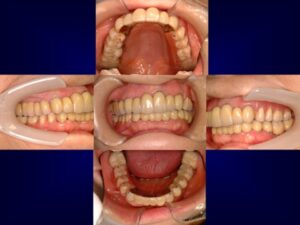

ケース3:インプラントを望まなかった40代女性

右上の奥歯を失い、保険義歯を使用していたが外れやすく人前で気になっていたとのこと。犬歯に引っかかる金属のクラスプも見えるのが嫌で、ほとんど外していたそうです。上顎をテレスコープ義歯にすることで外見と安定性が改善し、食事も会話も楽しめるようになりました。下顎は矯正やジルコニアによる修復も合わせて行い、全体の審美性も向上しました。

治療後は見た目が若返り、患者さん自身も非常に満足されていました。